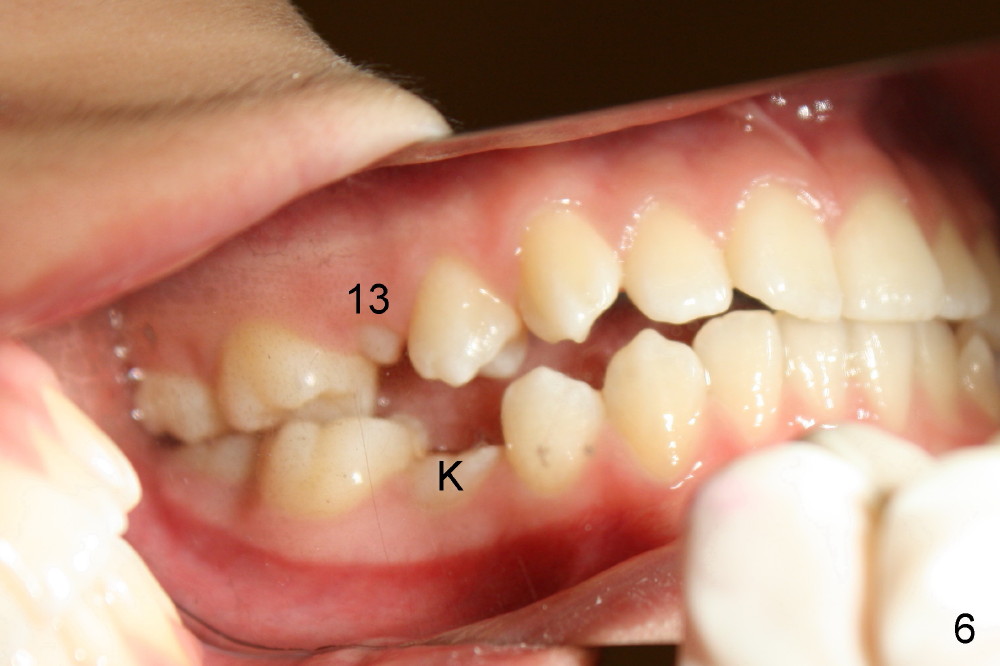

A 13-year-old Asian girl seeks orthodontic treatment for crowding. The lower 2nd bicuspids are congenitally missing (Fig.1,8), whereas the upper right one rotates 180° and the upper left is partially impacted (Fig. 1, 7). The lip muscles strain when the lips close (Fig.3). Orthodontic treatment started with extraction of four affected teeth (#4,13, K and T) 6 months ago. .018' niti wires are being used. Dental midlines do not coincide preop and intraop (Fig.4,4'). Pre-op front view shows that the upper dental midline coincides with the facial one (Fig.1'). There is Class I canine and molar relationship on the right (Fig.5,5',9,9'); open bite on the left (Fig.6,6',10,10').